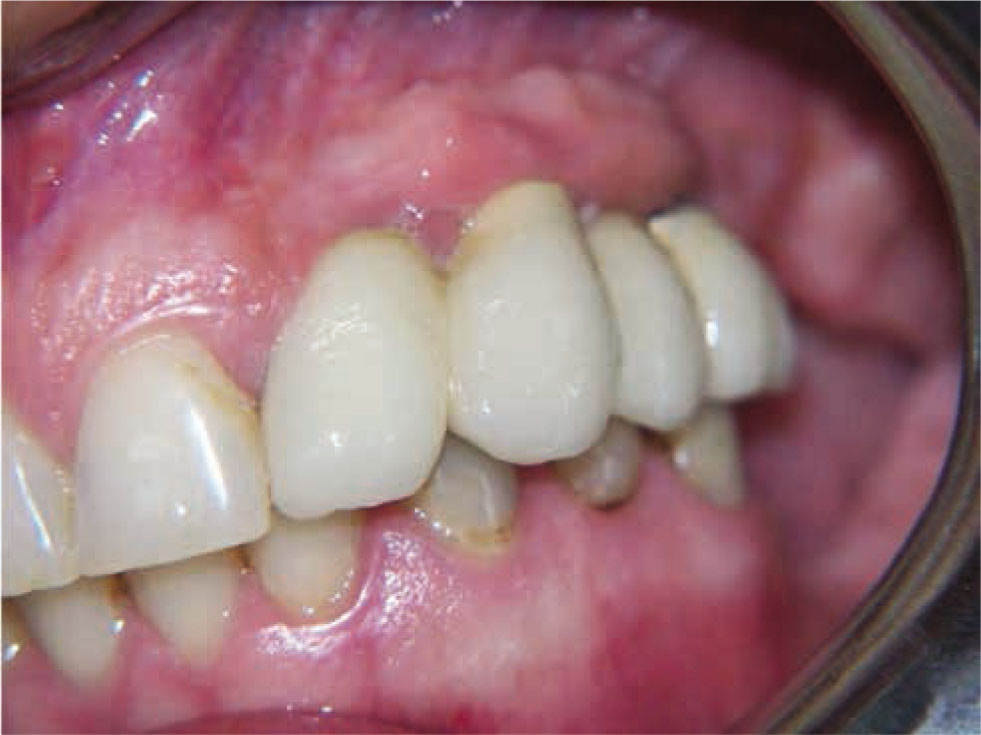

Figure 6 Final result and clinical oral view of a patient treated with the new flapless split crest procedure combined with PRF. Final aesthetic result obtained without any additional graft.

Figure 6

Final result and clinical oral view of a patient treated with the new flapless split crest procedure combined with PRF. Final aesthetic result obtained without any additional graft.